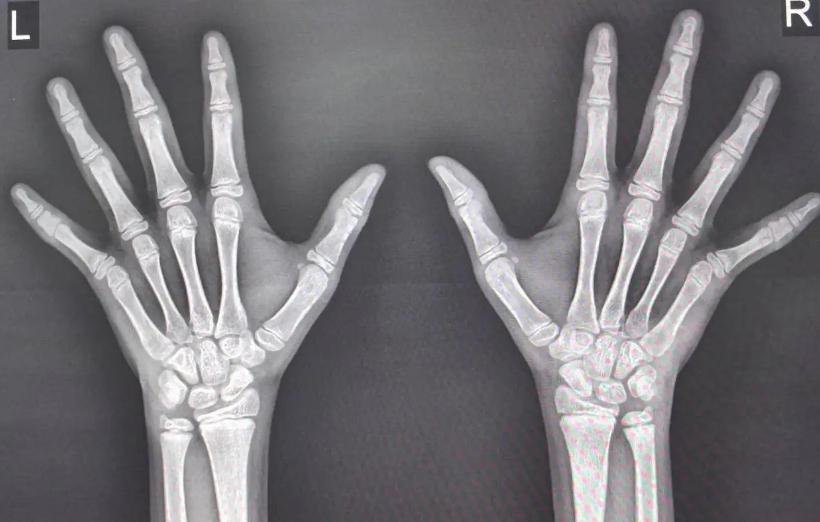

此外,另一处关键判断点是骨龄。医学影像上,专家通过手腕、掌骨等部位的X光片,评估孩子的骨龄是否“超前”或“滞后”。骨龄与实际年龄不一致,常暗示生长潜能是否尚未耗尽。如果骨龄已接近成人标准,哪怕孩子表面看起来还不足15岁,也意味着“可长身高指标”已接近上限。

骨龄检查同样不可或缺。中华医学会数据显示,通过手腕骨龄片可准确判断骨骺板是否闭合。一旦骨骺板呈现“闭合”迹象,哪怕身高还没有理想,后期增长空间也极为有限。某医院2023年就曾统计过:骨龄与实际年龄差不多的12岁男孩,未来平均还能长高5-7厘米;而骨龄超前的孩子,预期增长仅有2-3厘米。